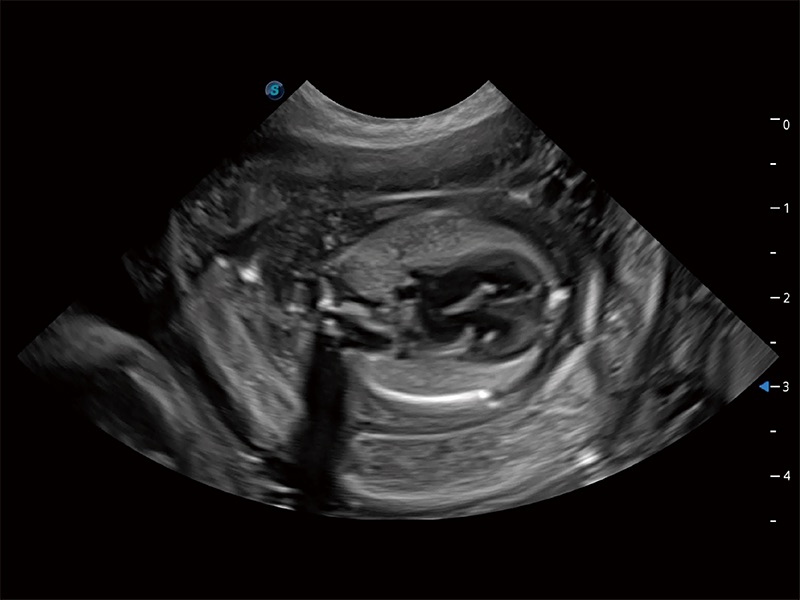

ProPet 80 配备了丰富的心脏探头群、先进的成像技术和专业的心脏测量工具,可帮助动物医生为不同体型和生理结构的动物提供心脏和心肌功能的全面评估。

实时用颜色表示心肌组织运动,观察和定量组织的运动情況,对快速检测与评估心肌的灌注和活性、电传导及心肌收缩和舒张功能等均能提供重要的诊断信息。

通过心肌识别技术与二维斑点追踪技术相结合,对心脏的超声图像进行量化分析。计算心肌17个节段的应变、应变率、速度、位移等,并通过牛眼图的形式进行呈现。

通过360度任意调节3条M型取样线,在同一心动周期上观察心脏不同位置的运动曲线,得到准确的心功能测量数据,有效评估心肌运动及左心室功能。

能够基于左心室壁追踪和辛普森法,自动计算射血分数,支持多个可移动点描迹,与手动测量相比,极大节省了动物医生的时间和精力。